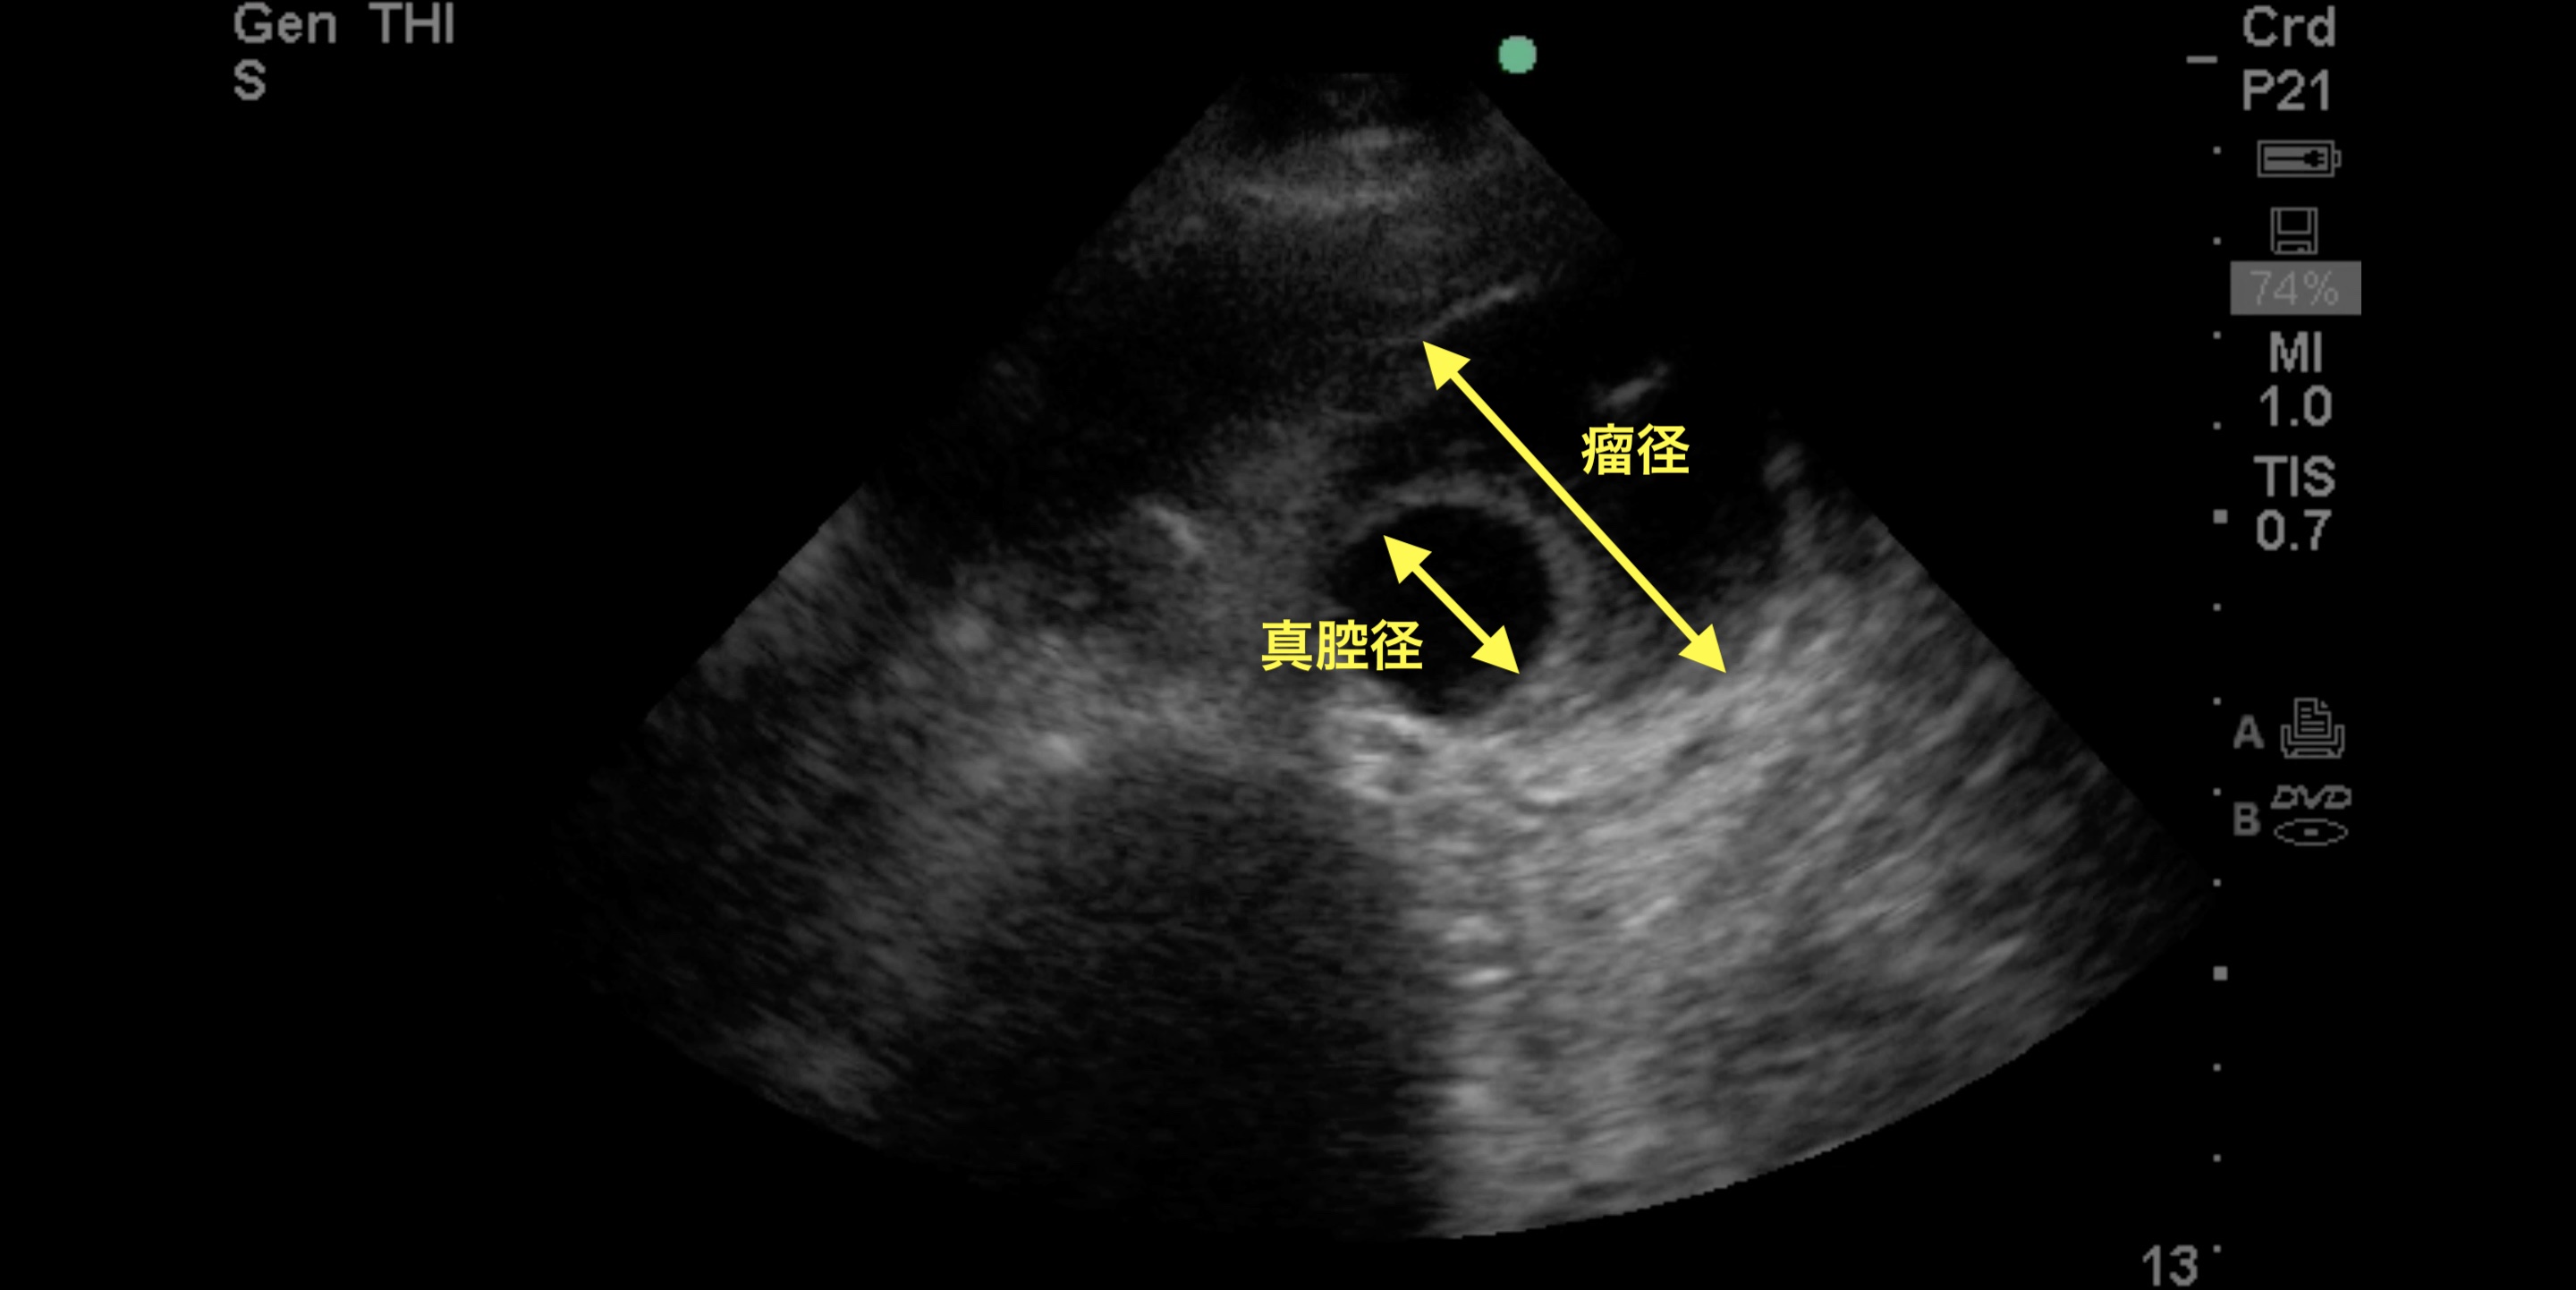

救急外来。腹痛。考えられる疾患はなにか?

腹部大動脈瘤

一般的に3cm以上で腹部大動脈瘤は定義されるが、径の測定には時に注意を要する。画像では、低エコー領域は中央の2-3cmの円形部分に限局しているが、その周囲を等エコーの壁在血栓が三日月状に囲んでいるため、実際の瘤径はそれよりもかなり大きいことが分かる。